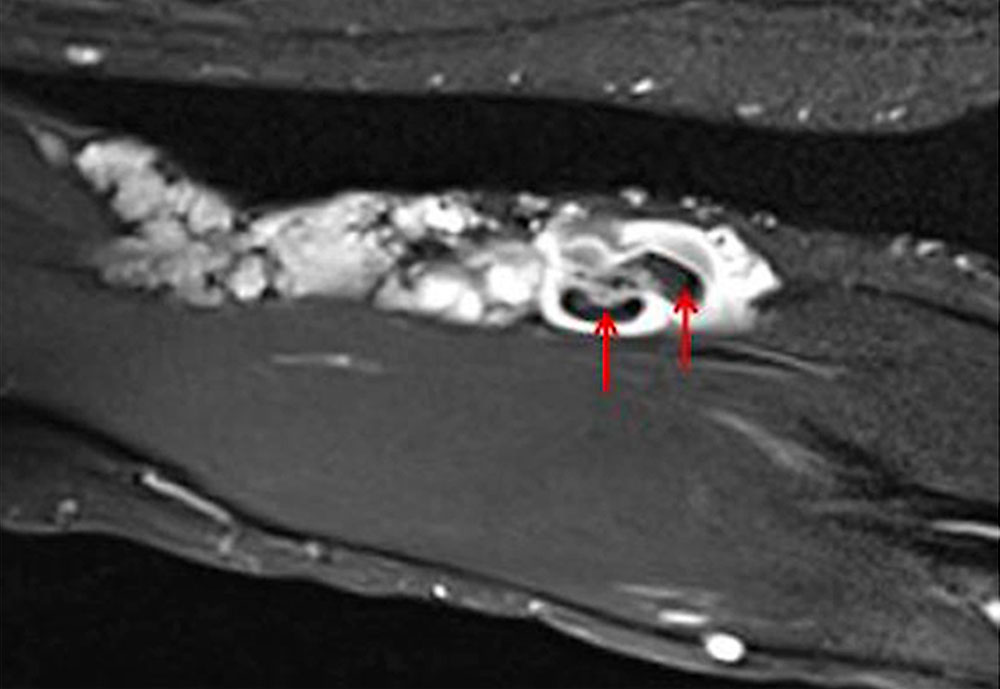

The normal organizing degradation of larger local thrombi or thrombophlebitis can lead to collagen deposition, which is palpable as a circumscribed induration over a longer period of time. If the thrombus then still cannot be completely degraded in the venous malformation, calcium deposition and increasing local, shell-like or popcorn-like calcification will occur over time. The final form is the calcified phlebolith as a round calcified lesion 1 cm in size on X-ray images of the venous malformation.

• Presence of multiple phleboliths within the venous malformation